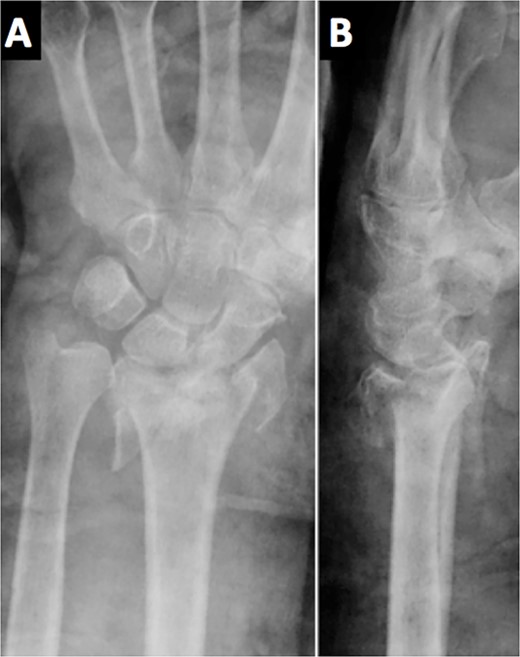

An 84-year-old, right-handed man attended the emergency room for the pain and swelling of his left wrist after a fall over his outstretched arm from a standing height. An X-ray was performed, showing an intra-articular comminuted fracture on the left distal radius, classified as 23-C3 according to the AO classification (Fig. 1). A cast was placed in the first place; meanwhile, the final treatment was decided.

The radiological images in the emergency department showed a comminuted intra-articular displaced fracture of the distal radius.